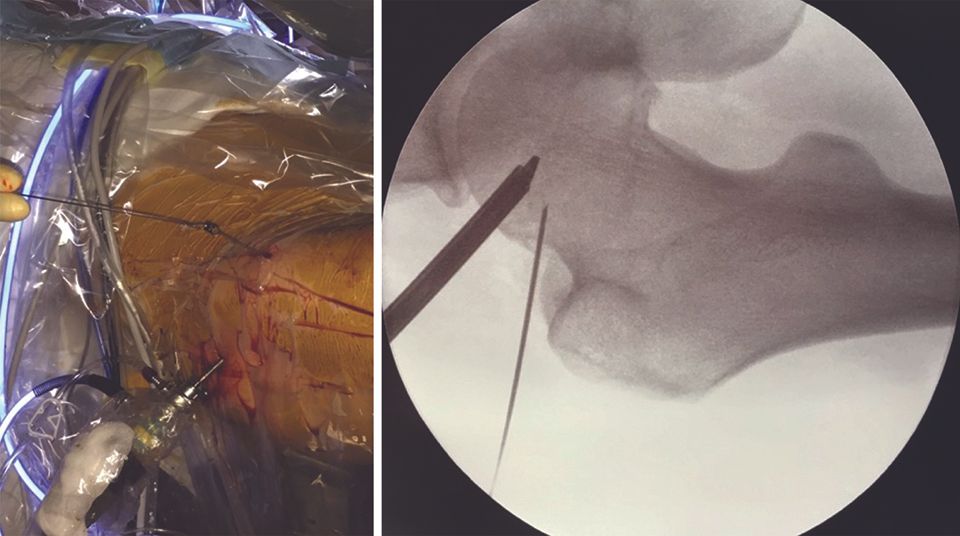

In my experience, the first point of entry is often situated mid-way between the ASIS and the apex of the greater trochanter (Fig. 13, left).

The needle is introduced, guided by the image intensifier, perpendicular to the superior part of the junction between the femoral head and neck (Fig. 13, right). Making small movements, the needle is used to probe along the lateral part of this junction to position it in the space between the anterior capsule and the anterior part of the junction between the femoral head and neck. Next, the nitinol guide is introduced, followed by the trocar for inserting the arthroscope.